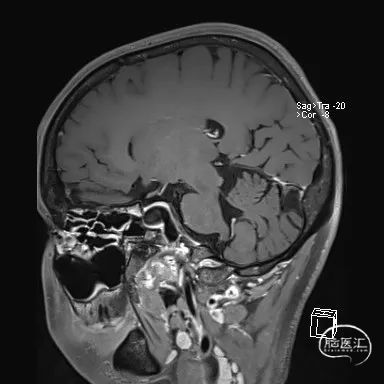

术前MRI平扫(T2):

左右滑动切换图片

高分辨MRI(提示夹层动脉瘤):